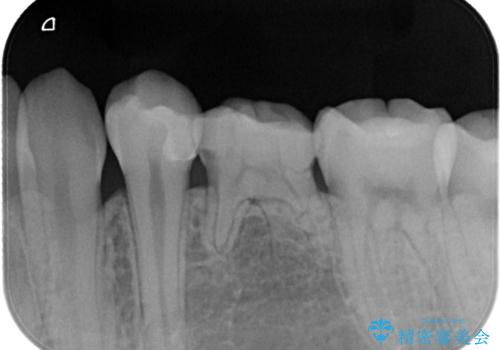

- 定期検診にてむし歯を認めたため、セラミックインレーにて修復を行いました。

e-max プレスインレーにて修復治療を行っているため適合性及び審美性の高い治療を行うことができます